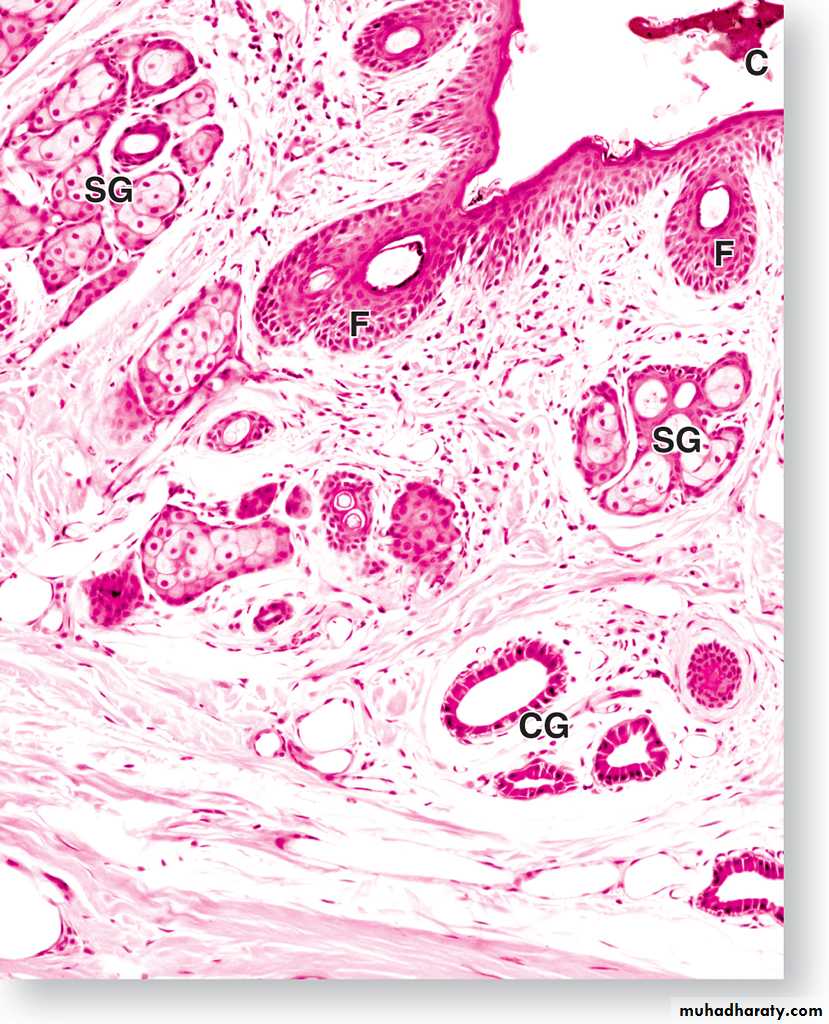

A section through the external auditory meatus,

(SG) sebaceous gland, (CG)ceruminous gland, (F) hair follicle,

(C) cerumen